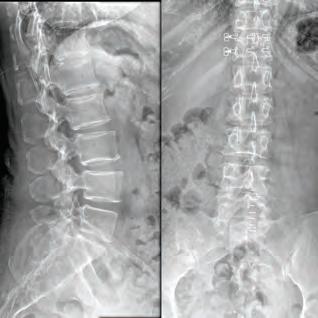

Our cover story this month features Dr. Stephen P. Courtney, a distinguished orthopedic spine surgeon whose commitment to his patients sets him apart in the medical community. Dr. Courtney’s career began humbly, working as an orderly in his teenage years, which sparked his passion for medicine. His academic and professional journey is nothing short of inspiring, having developed innovative spinal care technologies now patented under his name. Dr. Courtney applies a unique blend of hightech and high-touch approaches at Advanced Spine Center, ensuring that every patient receives the personalized care they deserve. Beyond his professional realm, Dr. Courtney is also an avid triathlete, illustrating the deep connection between physical endurance and personal health. Check out his story on page 8.

BOARD-CERTIFIED, FELLOWSHIP-TRAINED ORTHOPEDIC SPINE SURGEON PRACTICING FOR OVER 28 YEARS.

Ths realization inspired Dr. Courtney to design, develop, biomechanically test, complete FDA testing and oversee quality control and validation on a host of tools he created. To date, Dr. Courtney has developed nine spinal product lines and obtained nine patents and 14 trademarks on spine related products.

Led by Dr. Courtney, the skilled team at Advanced Spine Center cares for patients with neck and back pain using a wide array of the most state-of-the-art tools and techniques—from conservative physical therapy and injection therapy—to advanced pain manage-

ment, as well as surgical intervention. We employ the latest in minimally invasive spine surgeries, in addition to cutting-edge replacement technology. Incorporating both high tech and high touch, we get our valued patients back to their lives so they can enjoy all the activities they love.